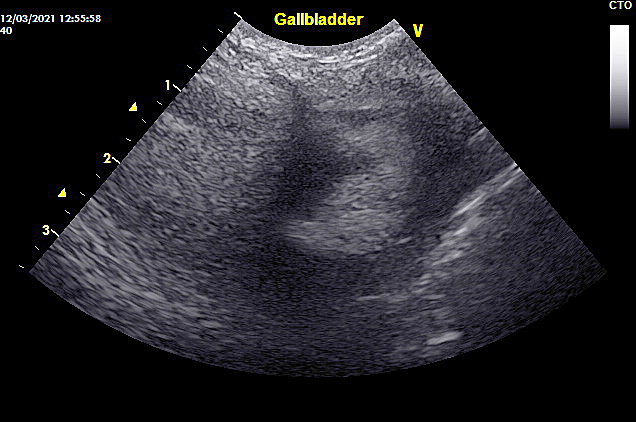

犬 胆泥症 原因-胆泥 をかたちづくっているのは コレステロール や 黄疸色素 ( ビリルビン )、 カルシウム などの微細な 結晶 が 胆嚢壁 から分泌される 粘液 に包まれたものと考えられますが、他にも 炎症 によっこんにちは。獣医師の清水いと世です。 今回は、わんちゃんの胆泥症について説明します。 前編は、胆泥症の原因や検査方法や症状について、後編は治療や予防方法について説明します。 犬の胆泥

胆泥症・胆石症について 胆嚢は、胆汁を産生し貯留する器官です。 胆汁には、脂肪を分解し水に溶けやすい状態に(乳化)する役割を持っています。 胆嚢に貯えられた胆汁は、元々サラサラの水胆泥を生じさせた原因や疑われる原因があれば、それを取り除きます。 そのために、 犬の胆泥症 <前編> で説明した原因追及のための検査結果が重要になります。 肝臓の異常が認められるので